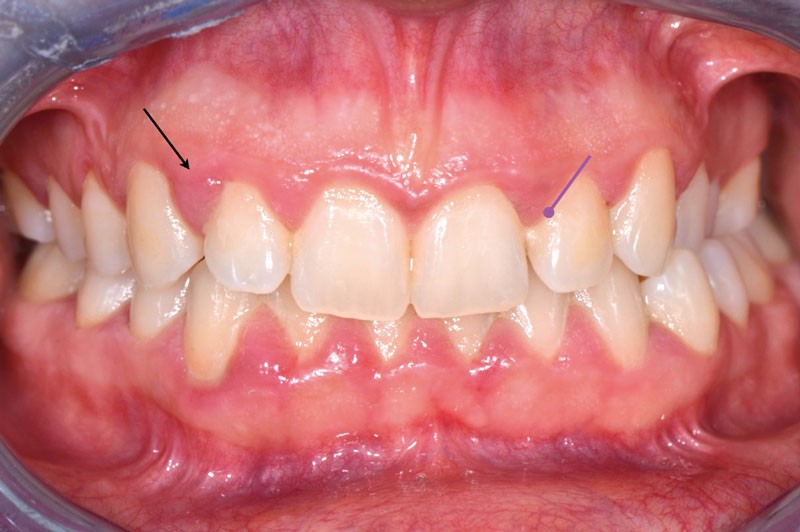

Ainsi, lors des périodes de désordres hormonaux, comme la puberté, la grossesse et la ménopause, on observe fréquemment des inflammations exacerbées qui peuvent révéler une susceptibilité de l’hôte aux maladies parodontales. (fig. 2 et 3).